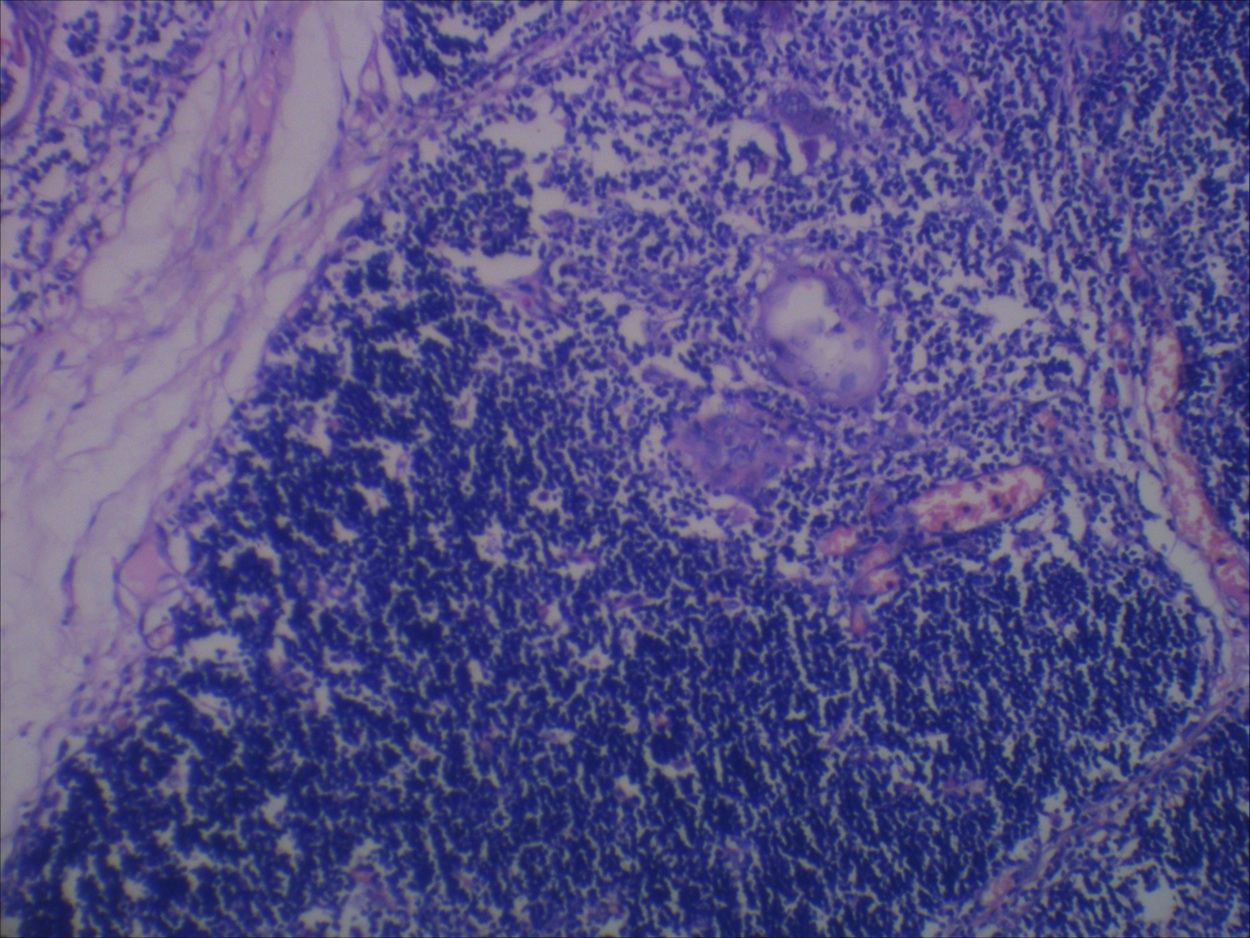

(A, B) Thymic hyperplasia the thymic architecture is conserved Thymic Hyperplasia Pathology Outlines True thymic hyperplasia is defined as increase in both size and weight of the gland while maintaining normal architecture. Thymomas are rare tumors arising from thymic epithelial cells with incidence rates of approximately 2.5 per million per year. Thymomas are rare before 25 years of age but show a wide age. Risk factors for thymoma are males with initial. 65%. Thymic Hyperplasia Pathology Outlines.